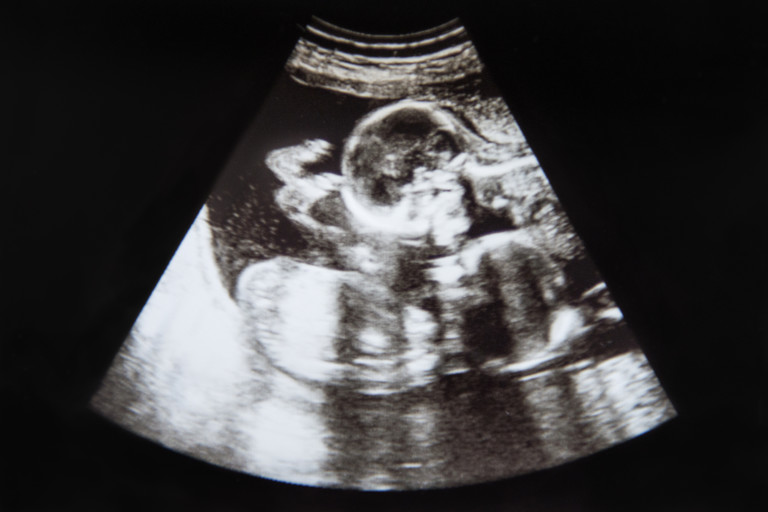

Много евентуално е явлението да бъде възприето като особеност от лекаря, защото той мери размера на ембриона, с цел да разбере неговата възраст. При съществуването на два ембриона с огромна разлика в размера, лекарят е по-вероятно да намерения, че при по-малкия има някаква особеност. Това може да се случи в доста ранните стадии на бременността при проучване с ултразвук.